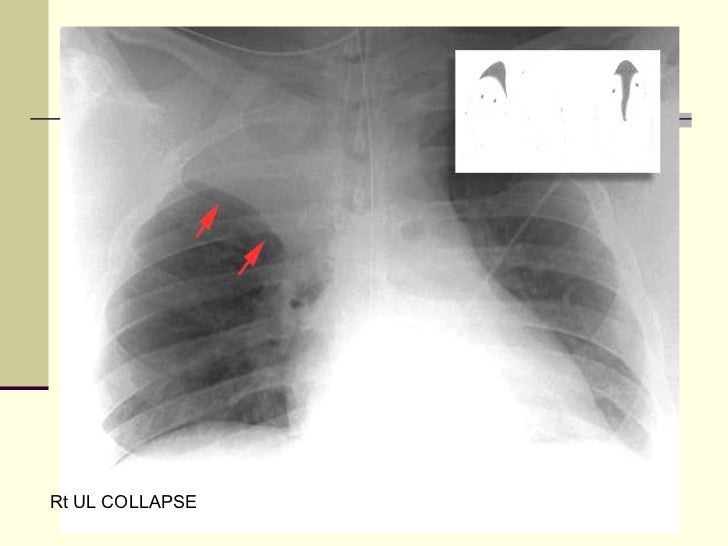

16. 16. Rt UL COLLAPSE